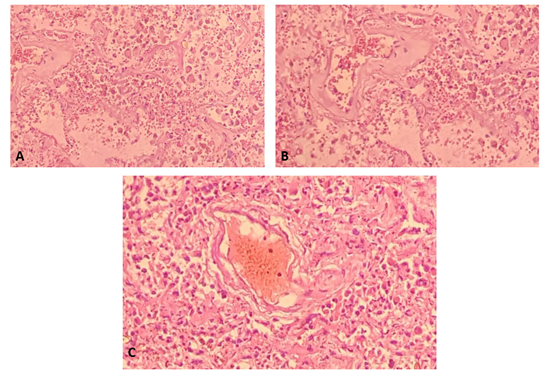

Post-mortem autopsy: it was performed to confirm severe SARS-CoV-2 infection, analyzing histological samples of lung tissue obtained by necropsy, determining the exact cause of death and recognizing histological patterns that eventually contribute to guide clinical management (Figure 3).

Figure 3 Histological changes observed in post-mortem autopsy.

A) Section of lung tissue shows pulmonary alveoli filled with acute inflammatory cells, macrophages. Increased fibro connective tissue in some alveolar septa and hyaline membrane formation resulting in respiratory distress.

B) Interstitial fibrosis, rupture of alveoar septa with acute intralaveolar and septal inflammatory response.

C) Vascular thrombosis associated with an inflammatory process and interstitial fibrosis.

The histological images translate what was evidenced in the imaging studies such as: diffuse alveolar damage in the organization phase with fibrosis, which was decisive for making therapeutic decisions, marking the patient's prognosis. In addition, the evidence SARS-CoV-2 testing can be done at autopsy. Autopsy findings such as diffuse alveolar damage and airway inflammation reflect true virus-related pathology. Other findings represent processes that are superimposed or not related to the disease under study. In this case, the patients with COVID-19 presented diffuse alveolar damage with the formation of hyaline membranes, mononuclear cells, and macrophages that infiltrate the air spaces, also with diffuse thickening of the alveolar wall.2

Wichmann et al also found a high incidence of thrombotic events, which suggests that the COVID-19 virus induces severe endotheliitis and abnormal activation of the coagulation cascade. For this reason, further studies are required to explain these findings, and eventually achieve a possible therapeutic intervention in the near future.2,6 Finally, Merad described micro thrombi at different levels in patients with COVID-19: lungs, lower extremities, hands, brain, heart, liver and kidneys, suggesting that coagulation activation and intravascular coagulation are data of an organic lesion in sepsis that is mainly associated with inflammatory cytokines and with the participation of the pathway tissue factor (abbreviated TF; also called CD142 or coagulation factor III) and which undoubtedly contributes to the greater severity of patients.2,7